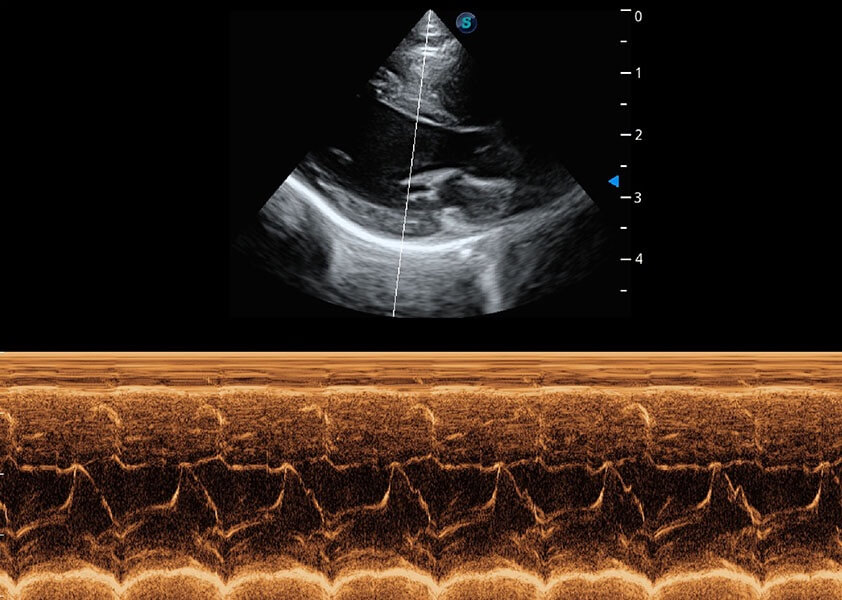

优异的基础图像

(犬)心脏组织多普勒

(猫)二尖瓣M型